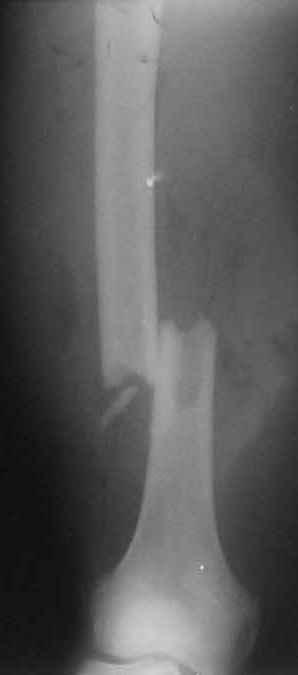

Р.S. Привожу клинический пример больного с огн. переломом бедра Густилло- Андерсон 111 А